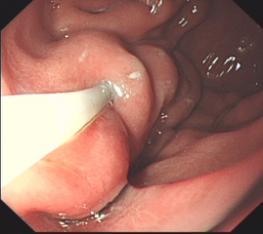

食管曲張靜脈出血套扎術(shù)